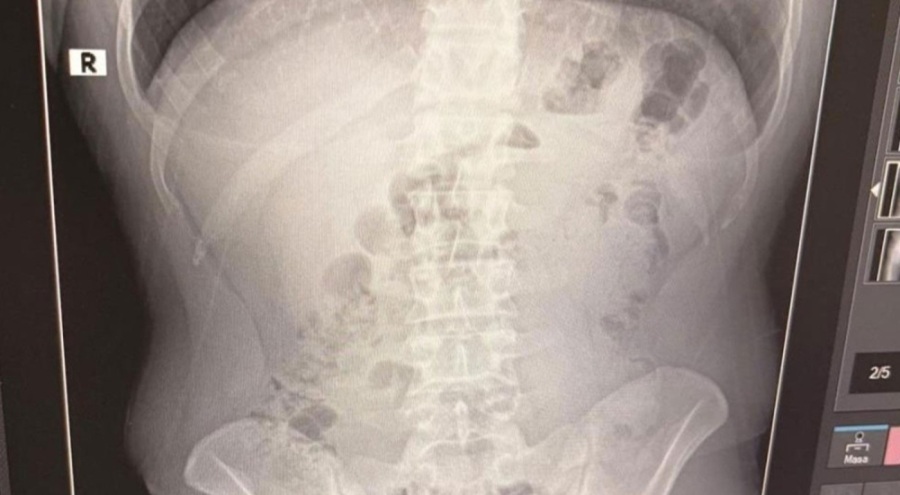

Adreste yapılan arama sırasında ekipler, şüphelilerden birinin üstünde 1 adet kapsül ele geçirdi. Şüphe üzerine tüm şüpheliler hastaneye götürüldü ve yapılan röntgen kontrollerinde 3 kişinin midelerinde kapsül içine gizlenmiş metamfetamin tespit edildi.

Hastanede tedavi altına alınan şüphelilerin vücudundan kapsüller çıkarılırken, adreste ele geçirilenlerle birlikte toplam 1 kilo 516 gram metamfetamin ele geçirildi.